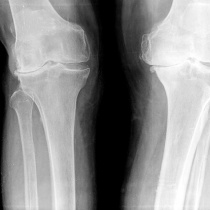

Les examens complémentaires de contrôle sont essentiellement ceux de l’imagerie médicale, qui permettent de suivre l’évolution de l’arthrose et éventuellement l’effet du traitement.